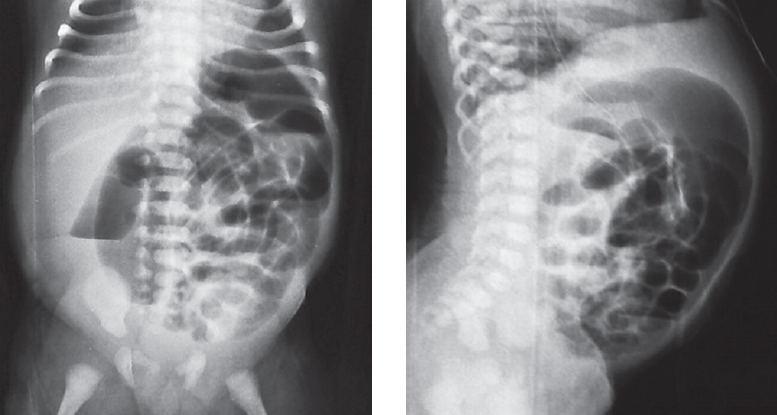

В хирургический стационар поступил ребенок на 2-е сутки жизни с клиникой кишечной непроходимости. По данным обзорной рентгенографии и ирригографии заподозрена болезнь Гиршпрунга (рис. 5, 6).

Рис. 5. Обзорная рентгенограмма брюшной полости

Fig. 5. Plain abdominal X-ray

Рис. 6. Ирригография

Fig. 6. Contrast enema

После выполнения высокой очистительной клизмы получено большое количество жидкого стула, газов, живот уменьшился в размерах. Планировалось продолжение консервативного лечения в виде ежедневных сифонных клизм и антибактериальной терапии. Однако через сутки произошло ухудшение состояния, наросло вздутие живота. Выполнены повторные рентгенограммы брюшной полости, выявлен свободный газ. Ребенок подготовлен к оперативному лечению в срочном порядке. При ревизии брюшной полости обнаружена перфорация толстой кишки в области илеоцекального угла. Восходящая и поперечно-ободочная кишки были умеренно расширены до 2–3 см, а от селезеночного угла до ректосигмоидного отдела кишка воронкообразно суживалась до 0,8–0,6 см. Интраоперационная картина соответствовала представлению о болезни Гиршпрунга, но оценить протяженность зоны аганглиоза не представлялось возможным. Нельзя было исключить тотальный аганглиоз толстой кишки, поэтому была наложена двойная илеостома и взята поэтажная биопсия толстой кишки, перфорационное отверстие ушито. Удивительными оказались результаты гистологического исследования, которое показало, что нервный аппарат толстой кишки сформирован правильно. Однако обнаружено тотальное грибковое поражение кишечной стенки во всех отделах, что, возможно, и явилось причиной перфорации толстой кишки. Послеоперационное течение без хирургических осложнений. Через 2 мес. выполнено закрытие илеостомы. Выздоровление.

Ирригография является обязательным исследованием у всех детей с подозрением на болезнь Гиршпрунга [2]. Чувствительность и специфичность метода по литературным данным достигает 70 и 80 % соответственно. Хорошо известно, что диагностическая значимость ирригографии в определении переходной зоны у новорожденных с болезнью Гиршпрунга меньше, чем у детей более старшего возраста (65 против 75 %) [3]. I.R. Diamond et al [4]. описали возможные предрасполагающие факторы получения ложноположительных результатов при выполнении контрастного исследования у пациентов с болезнью Гиршпрунга, одним из них является возраст ребенка. У детей в возрасте 30 сут жизни было больше ложноположительных результатов, чем у пациентов младшего возраста. Срок выполнения рентгенологического обследования зависит от нескольких факторов, главным из которых является эффективность опорожнения толстой кишки. Обследование целесообразно выполнять не сразу после поступления новорожденного в стационар, а отсроченно, после купирования явлений Гиршпрунг-ассоциированного энтероколита, чтобы исключить сужение кишки, связанное с ее спазмом на фоне воспалительных явлений. Конечно, это не касается ситуаций, когда есть клиника некупирующейся кишечной непроходимости, либо признаки «токсического» мегаколона. В этих случаях ирригография обязательно проводится непосредственно при поступлении ребенка в стационар. В остальных случаях, когда декомпрессия кишечника эффективна, исследование может быть отложено на несколько дней, до полной стабилизации состояния и нормализации клинико-лабораторных показателей. Контрастирование толстой кишки у детей с клиникой низкой кишечной непроходимости носит не только диагностический, но и лечебный характер, особенно при синдромах мекониальной пробки и суженной левой половины толстой кишки, которые могут быть причиной для постановки ложноположительного диагноза болезни Гиршпрунга. Надо отметить, что ирригография, выполненная в первые дни жизни ребенка сразу после появления клиники непроходимости, и отсроченное исследование могут отличаться друг от друга. На представленных рентгенограммах одного и того же ребенка с разницей в две недели видны существенные различия (рис. 8, а, b). Если на первичной ирригограмме можно оценить лишь правильность расположения толстой кишки и наличие в ней большого количества содержимого, то при исследовании через 2 недели видны четкие признаки ректосигмоидной формы болезни Гиршпрунга с наличием зоны сужения и воронкообразным супрастенотическим расширением.

Рис. 8. Ирригография; а — вторые сутки жизни; b — две недели жизни

Fig. 8. Contrast enema. а – second day of life; b – two weeks of life

Еще одним доводом за выполнение отсроченных ирригограмм у новорожденных с подозрением на болезнь Гиршпрунга может служить тот факт, что при раннем исследовании можно увидеть выраженное сужение толстой кишки, которое у новорожденного может быть признаком не только аганглиоза, но и иметь другие причины.

Считается, что чем более выражена разница в диаметре кишки при ирригоскопии, выполненной в первые дни жизни ребенка, тем менее вероятна болезнь Гиршпрунга. В этом плане очень показателен случай 3. В той ситуации дифференцировать болезнь Гиршпрунга от грибкового поражения толстой кишки до операции было практически невозможно. С подобной картиной мы встретились впервые. Рентгеноконтрастное исследование толстой кишки в данном случае не имело диагностической ценности.